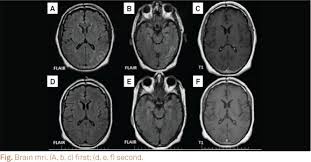

Guillain Barre Syndrome Associated With Central Nervous System Lesions Archives Of Disease In Childhood

Guillain Barre Syndrome Associated With Central Nervous System Lesions Archives Of Disease In Childhood from adc.bmj.com

Cerebral magnetic resonance imaging showed lesions in both frontal and right occipital lobes. Mri is sensitive, but nonspecific, for diagnosis. During a course of intravenous immunoglobulin therapy, she had headache with meningism. The most common result is a weakness and numbness that starts at the tips of the fingers and toes and spreads inward toward the body. Mr imaging findings in eight patients (three male, five female; 1 article features images from this case 14 public playlist includes this case Although no abnormalities were observed on brain and spinal magnetic resonance imaging and electroencephalography, peripheral nerve conduction velocity tests failed to evoke motor and sensory nerve action potentials. Typically, both sides of the body are involved, and the initial symptoms are changes in sensation or pain often in the back along with muscle weakness, beginning in the feet and hands, often spreading to the arms and upper body.